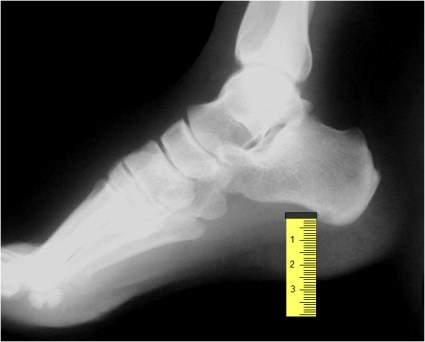

SIGNO DE LA C

Signo de coalición subtalar (fusión calcáneo-astragalina) en la radiografía lateral del tobillo. La «C» se forma por el límite medial de la cúpula talar y el límite posteroinferior del sustentaculum tali.

En la radiografía lateral de tobillo hemos marcado con flechas la «C» que da nombre al signo.

La fusión calcáneo-astragalina (flecha) se comprueba en el corte coronal de TC de tobillo.

Referencia: Lateur LM y cols. Subtalar coalition: diagnosis with the C sign on lateral radiographs of the ankle. Radiology 1994; 193: 847-851.